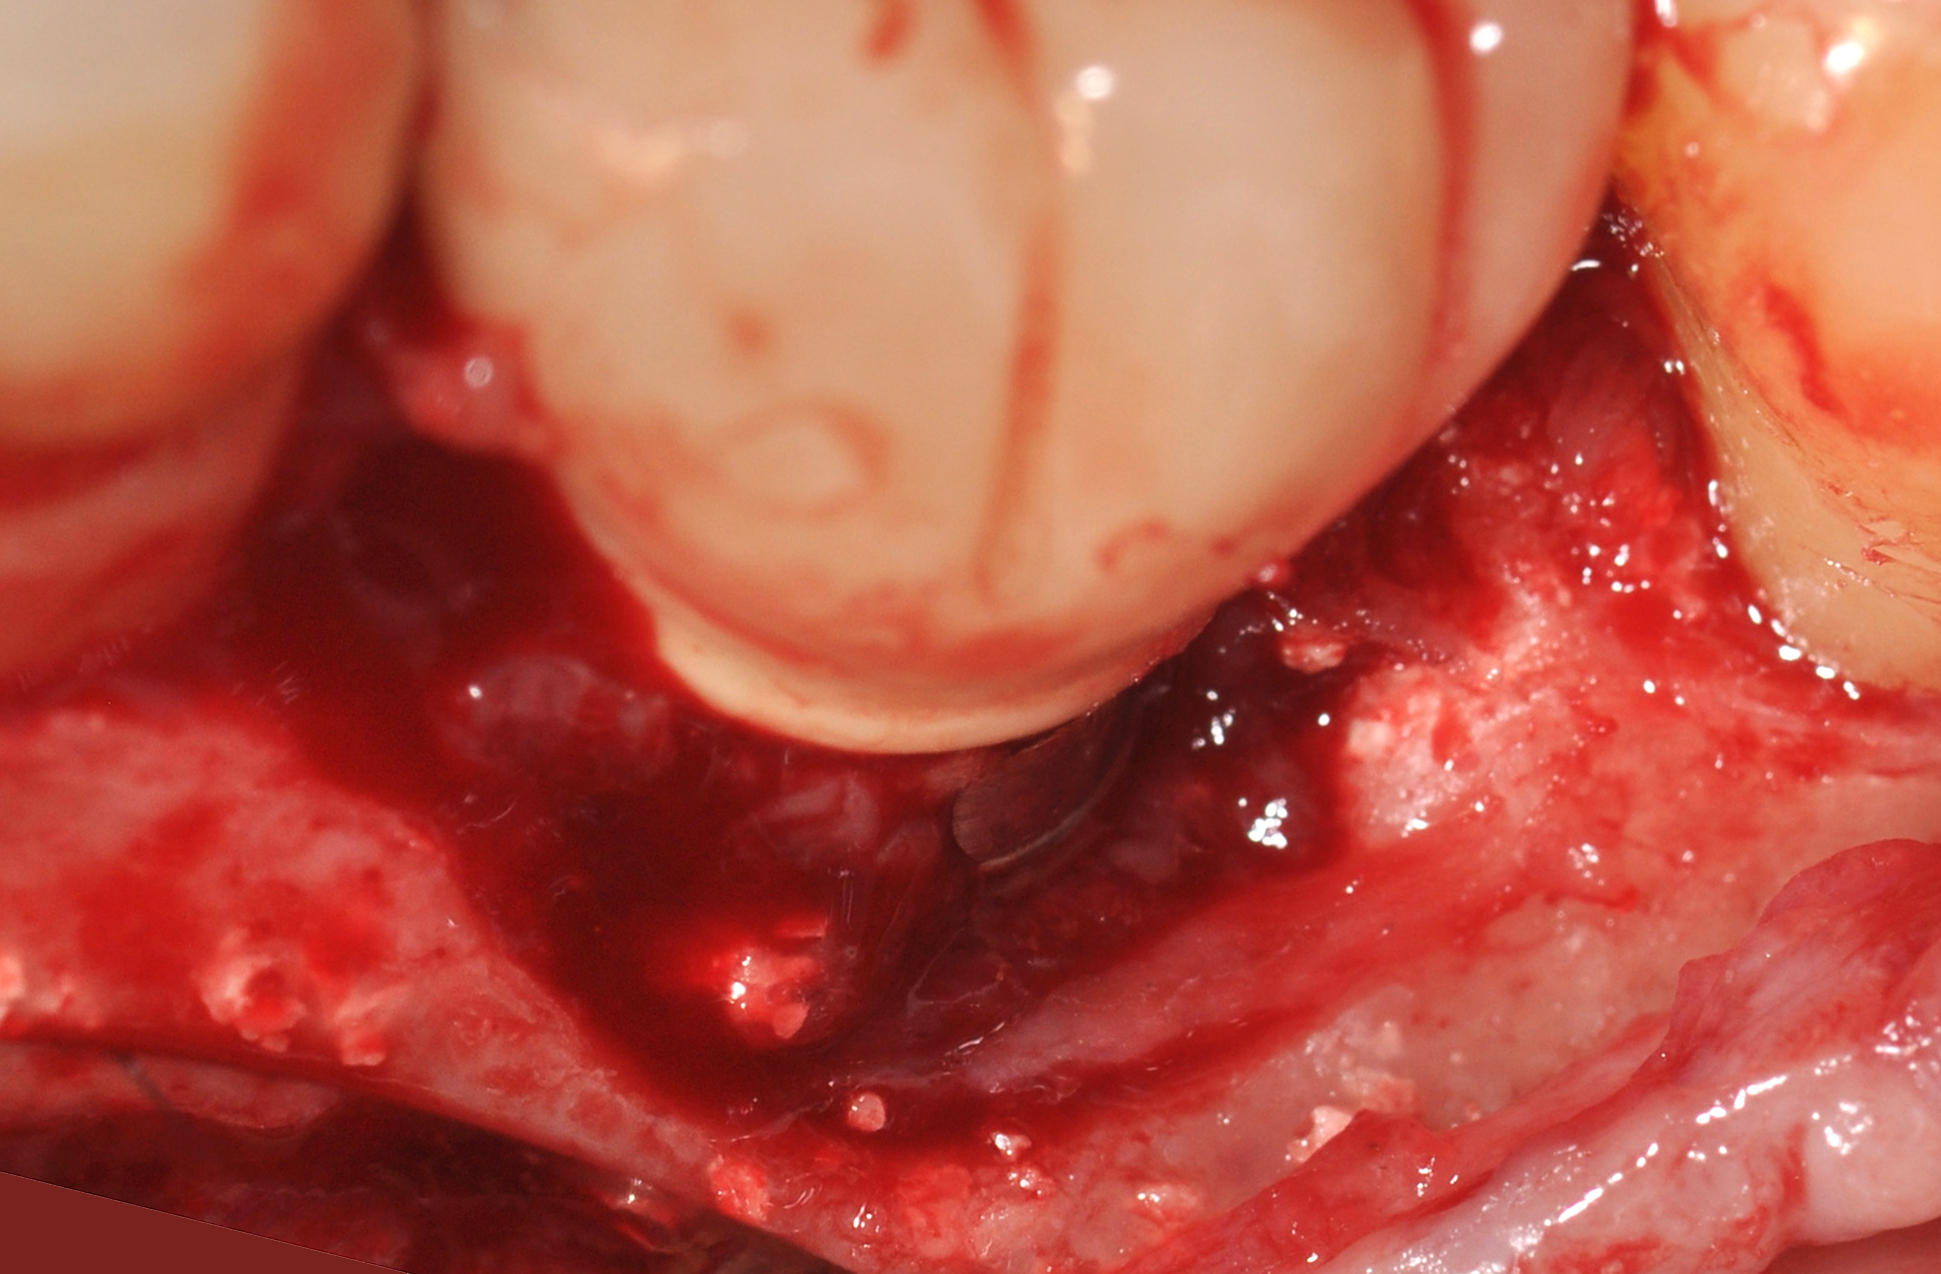

A surgical flap procedure was performed with the intent of thoroughly debriding the granulomatous tissue from the osseous defect (Figure 18 and Figure 19), mechanically and chemically detoxifying the surface of the implant (Figure 20 through Figure 22), and grafting the infrabony component of lesion with bone xenograft (Bio-Oss®, Geistlich Pharma, www.geistlich-na.com) in an attempt to reduce the vertical defect (Figure 23). To concurrently resolve the mucogingival problem, the plan called for placing a dermal allograft (Dermis Allograft, DENTSPLY International, www.dentsply.com) on the buccal (Figure 24) and then replacing the flap (Figure 25).

Fig 18. A full-thickness flap from teeth Nos. 18 to 20 revealed granulomatous tissue in the circumferential defect around implant No. 19.

Fig 19. The circumferential defect was debrided. Note excess cement extending apically from the margin of the crown into the defect; residual cement has been shown to be complicit in the development of peri-implant disease.